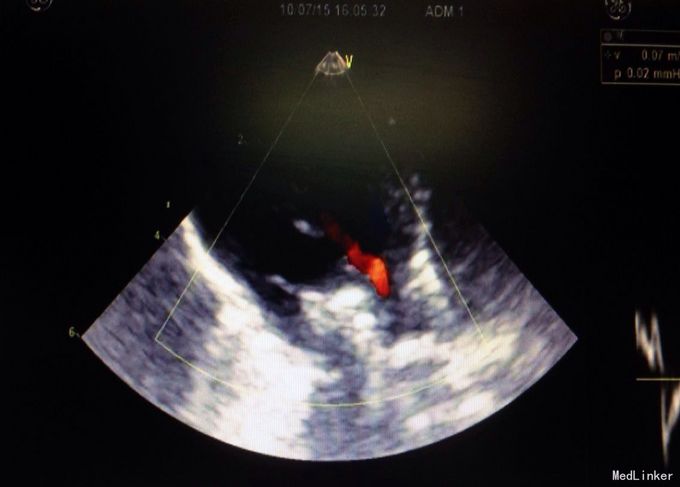

体检:生命体征正常,全身皮肤黏膜无黄染,腹隆,肝脾肋下未及,宫高29,腹围88, FHR148,头位,未触及宫缩,未行内诊,骨盆外测量22-26-18-8 辅助检查:2周前外院检测总胆汁酸25umol/L,一周前复查总胆汁酸60umol/L,今日外 院B超示晚孕,单活胎,头位,胎儿房间隔中部囊样无回声,考虑膨胀瘤可能,本院检查 结果如下图

入院诊断:孕39周待产,G2P1,ICP 诊疗经过:患者入院后给予护肝等对症支持治疗,顺娩1活女婴,分娩后子宫收缩好,新 生儿心脏彩超示动脉导管未闭,拟随访。